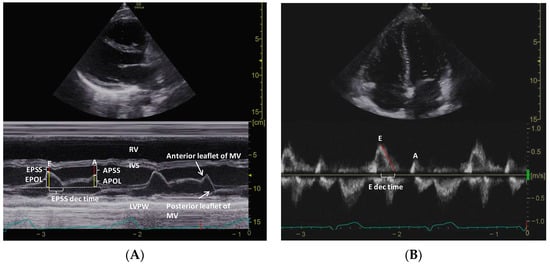

2.4. M-Mode Measurements in PSLA View

This study used the M-mode technique to obtain mitral valve separation measurements in the PSLA view. Specifically, EPSS refers to the separation distance between the anterior leaflet and the septum during early diastole. Additionally, the distance between the anterior leaflet of the MV and the interventricular septum during late diastole is defined as the A-point septal separation (APSS). Furthermore, the investigators measured the vertical distance between the imaginary line where the MV is closed at systole and the tip of the anterior leaflet of the mitral valve during early diastole, which is defined as the E-point opening length (EPOL). Similarly, the distance to late diastole is defined as the A-point opening length (APOL). Using the M-mode technique, the time between the peak early diastolic point and nadir (EPSS deceleration time) was obtained (Figure 1A). To ensure reproducibility, M-mode measurements were performed twice in the PSLA view, and the time required for M-mode measurements was recorded only during the first measurement.

Figure 1. M-mode measurements of MV anterior leaflet in the PSLA view (A) and PW Doppler measurements in the A4C view (B).

MV, mitral valve; PSLA, parasternal long axis; PW, pulsed-wave; A4C, apical 4-chamber; EPSS and APSS, E-point and A-point septal separation; EPOL and APOL, E-point and A-point opening length; RV, right ventricle; IVS, interventricular septum; LVPW, left ventricular posterior wall; E and A, early and late diastole velocity of the mitral inflow; E dec time, E deceleration time.

PW Doppler was used to obtain mitral inflow measurements, which included the peak trans-mitral inflow velocities during early diastole (E) and late diastole (A), the E/A ratio, and the deceleration time of early diastolic flow (E deceleration time) (Figure 1B). Tissue Doppler imaging (TDI) in the A4C view was used to obtain the septal mitral annular excursion velocity (e’) in early diastole. The measurement times for the E/A ratio and the E/e’ ratio were recorded, and the LV ejection fraction (EF) was measured using Simpson’s method.